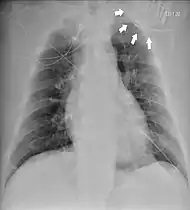

| Chest radiograph showing twiddler's syndrome. The leads of the automated external defibrillator are wrapped around the device and can't be seen in the ventricle. | |